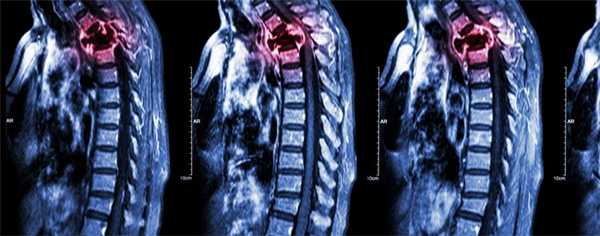

Метастазы в позвоночнике

Метастазы в позвоночнике - это очаги злокачественного поражения в костной ткани, образованные раковыми клетками, отделившимися от первичной опухоли и распространяющимися в организме с током крови или лимфы. По статистике, метастазы составляют 90% всех злокачественных новообразований в позвоночнике. Они нарушают опорную функцию позвоночного столба, способны привести к сдавлению спинного мозга, нервных корешков, тяжелым неврологическим нарушениям.

Многие типы рака метастазируют в кости, чаще всего в позвонки. В большинстве случаев опухолевые клетки распространяются гематогенно — с током крови. Вторичные очаги ослабляют костную ткань, это грозит патологическими переломами позвонков, которые приводят к сильным болям, существенному снижению качества жизни, сдавлению спинного мозга и нервных корешков.

В 95% случаев метастазы в позвоночнике являются экстрадуральными, то есть находятся за пределами твердой мозговой оболочки. Более чем в половине случаев очаги локализуются на разных уровнях позвоночного столба.

Диагностика метастазов в позвоночнике

Основные методы диагностики — КТ и МРТ. Они помогают детально визуализировать структуры позвоночного столба, опухолевую ткань. Рентгенография менее информативна, так как на снимках видны только костные структуры, обычно ее применяют при подозрении на патологический перелом.

Прогноз при раке 4 стадии с метастазами в позвоночнике

Прогноз зависит от типа первичной опухоли. Средняя выживаемость составляет 10 месяцев. Прогностически неблагоприятный признак — сдавление спинного мозга. При этом средняя выживаемость составляет 3 месяца.